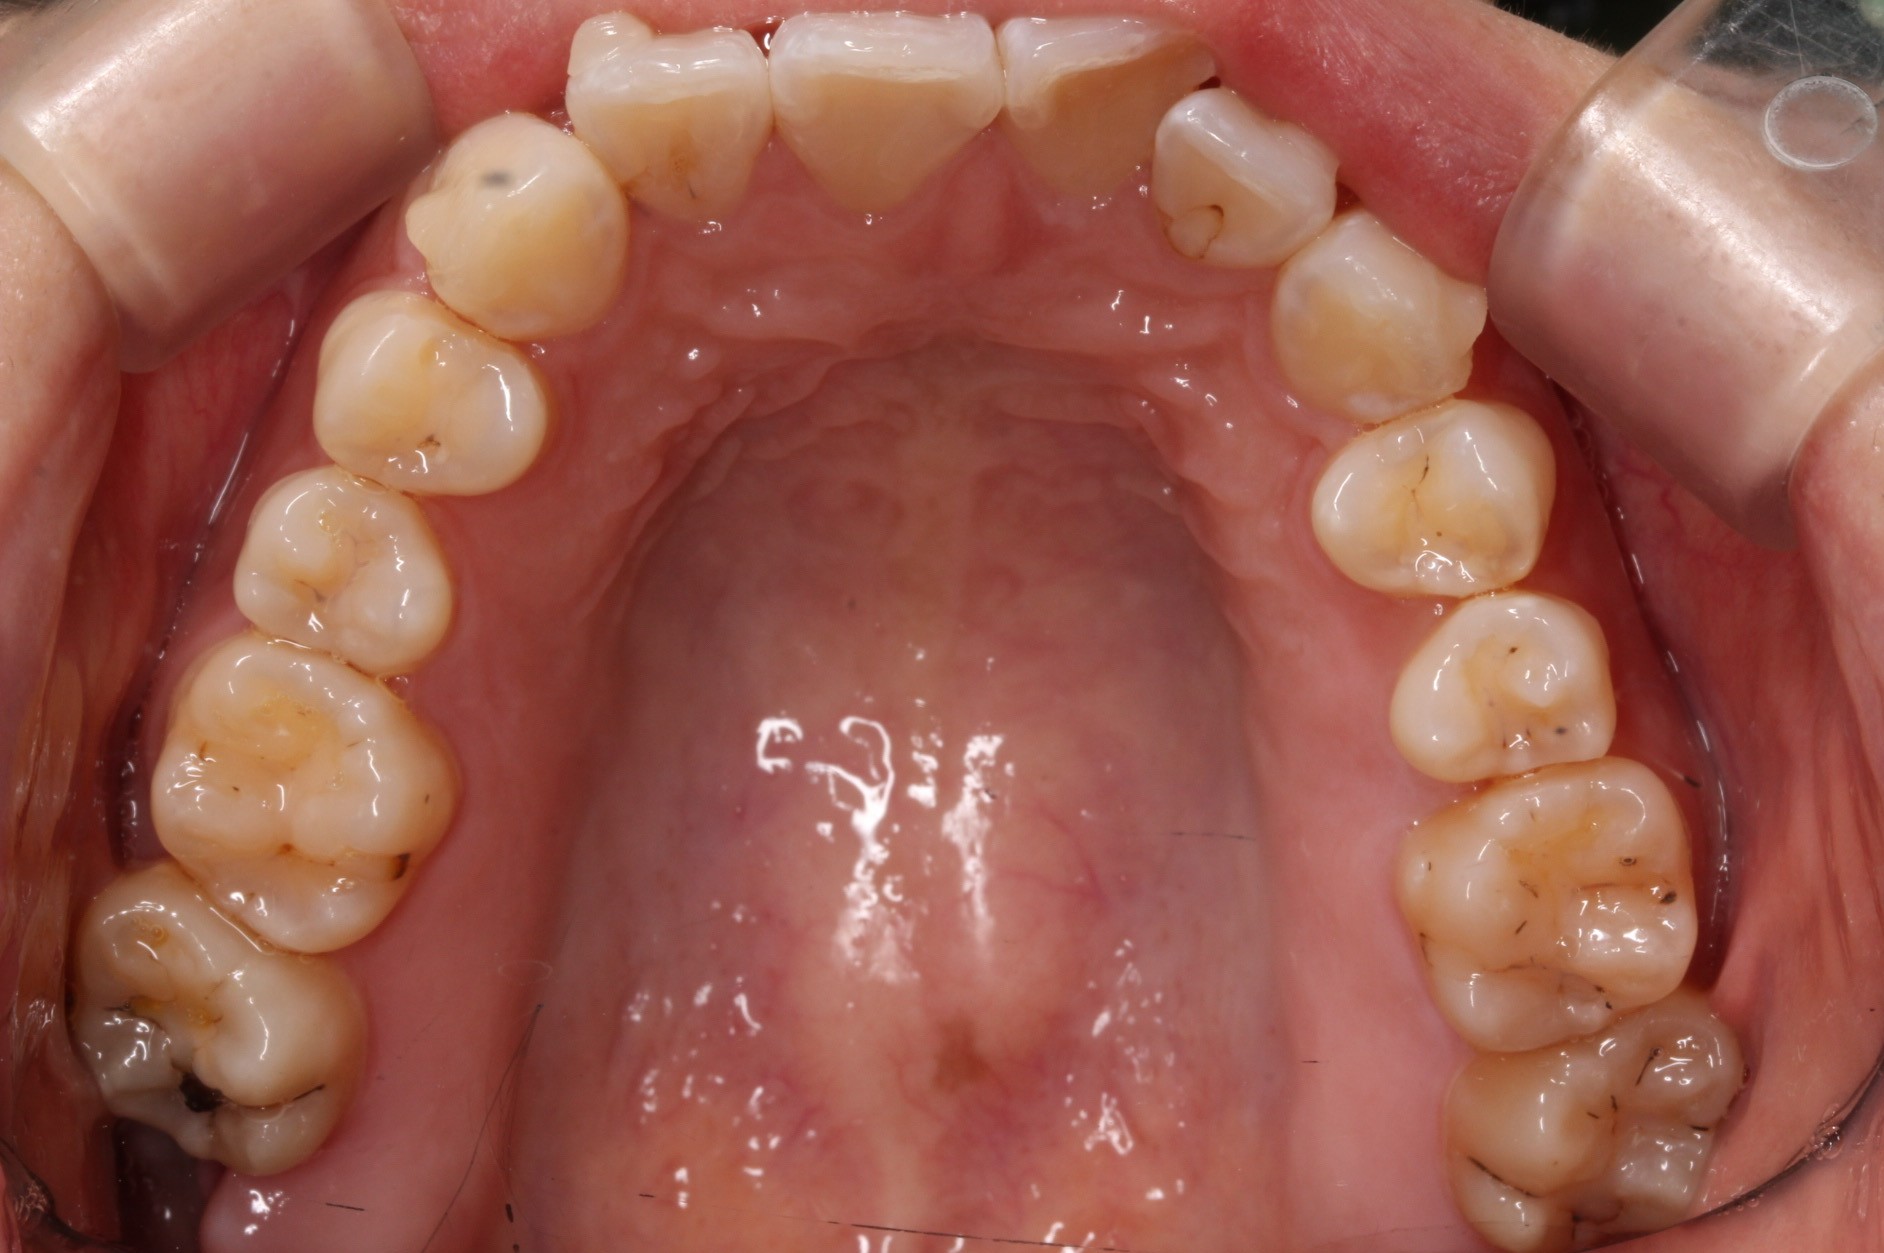

矯正術前:上顎

矯正術後:上顎